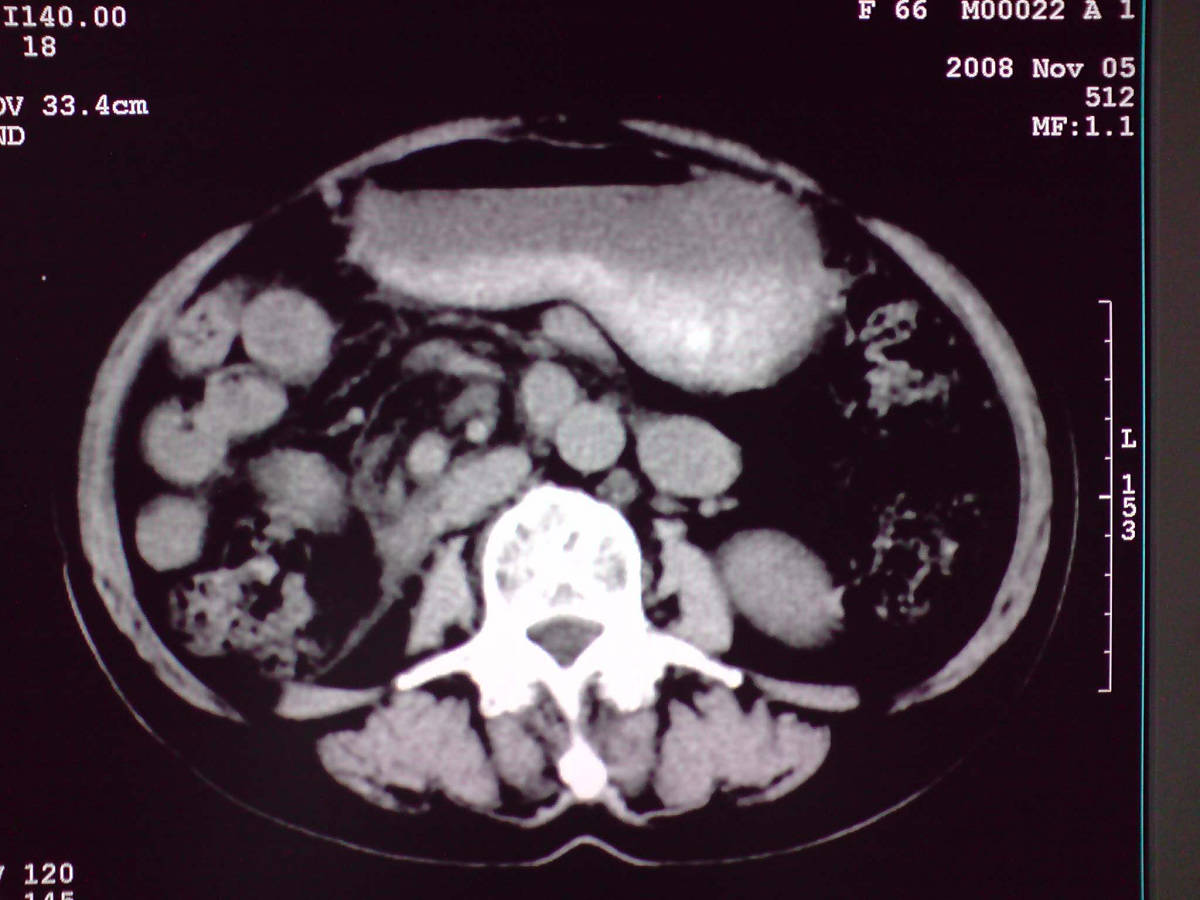

小网膜区见类圆形软组织密度肿块,密度不均,内见不规则低密度区,与肝左叶分界模糊,肝脏体积缩小,密度不均匀,边缘呈波浪状,尾状叶明显增大,脾脏下缘明显超出肝脏下缘。

意见:肝硬化并外生性肝癌,建议增强扫描。

肝脏比例失调,形态失常,外缘呈波浪状,腹腔内肿块内见低密度区并与肝脏界限欠清

考虑外生性肝癌,左肺下叶占位,肝硬化

有肝硬化背景,肝胃间隙见不规则形,且密度不均匀的占位性病变,与肝左叶分界不清,首先考虑外生性肝癌可能性大,不排外肝胃间隙恶性占位肝脏受侵可能性。左肺下叶结节影,其内见空泡征,边缘见毛刺,从一元化的角度首先考虑转移。

1 肝脏各叶比例失调,形态失常,外缘呈波浪状。右叶萎缩,左叶 尾叶增大。2 腹腔内软组织密度肿块,低于肝实质密度,内见低密度区,并与肝脏界限欠清。腹膜后见肿大淋巴结,并与腹腔肿块关系密切。3 左肺下叶肿块,见边缘毛刺征及胸膜凹陷征,并与近肺门侧见异常血管相连。

综合考虑:左下肺周围性肺癌伴腹腔 腹膜后淋巴结转移!另:肝硬化!

肝脏比例失调,形态失常,外缘呈波浪状,腹腔内

小网膜区肿块内见低密度区并与肝脏界限欠清

1肝胃韧带区域一肿块,肿块上缘与肝左叶相连。肝硬化。考虑肝外生型肝癌可能性大,不除外间质瘤。2左肺下叶背段一结节,有偏心性空洞,长毛刺,其周有多发小结节。考虑结核可能性大。